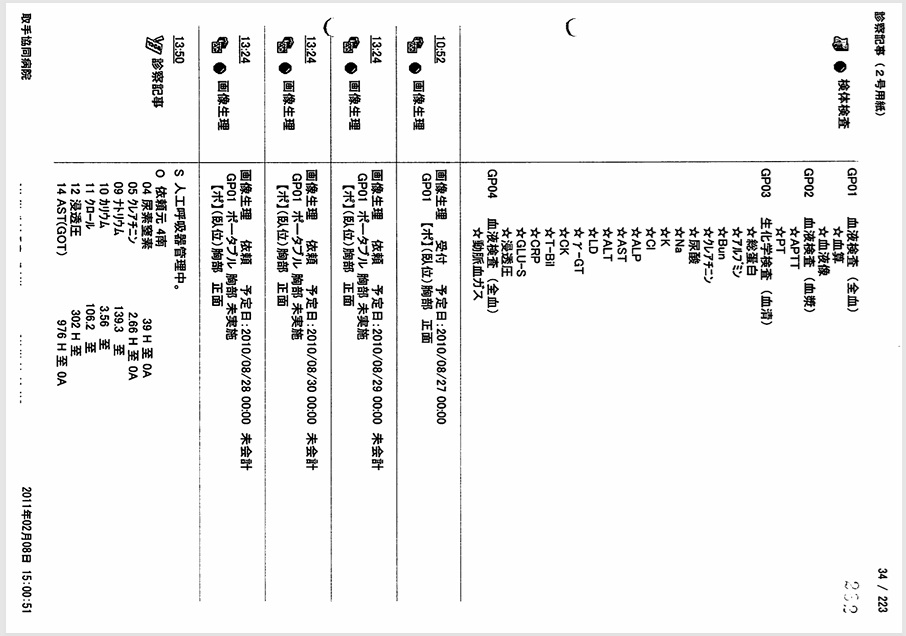

- 8月27日:APTT 92秒でヘパリン増量(死期を故意に早めようとした疑い)

胸腔、心嚢内への出血によるショックの進行中、8月27日の血液検査でAPTT 92秒とパニック値にもかかわらず、ヘパリンを15000単位から20000単位に増量。故意に死期を早めようとした疑い。

証拠:血液検査・注射処方箋の抜粋(赤枠部分)

- 8月27日:医師・看護師、心嚢水増量、危険な状態を認識

当日のカルテには「心嚢水増量」、「危険な状態」との記載あり。

証拠:カルテ記載

8月27日の午後3時の時点で、血圧60/40 mmHg, 心拍数150~160/min、8時間尿量4mlと、いつ心肺停止してもおかしくない状態であった。 しかし医師は父がショックに陥った原因を「元々の心筋梗塞が重症のため」と偽り、 医療事故とそれに起因する緊張性血胸・心タンポナーデ、出血性ショックを隠蔽した。 またヘパリン15000単位/日が投与されていたが、この日の血液検査でAPTT 92秒とヘパリン投与量が過剰であったにもかかわらず、ヘパリンが20000単位/日に増量されており、故意に死期を早めようとした疑いがある。